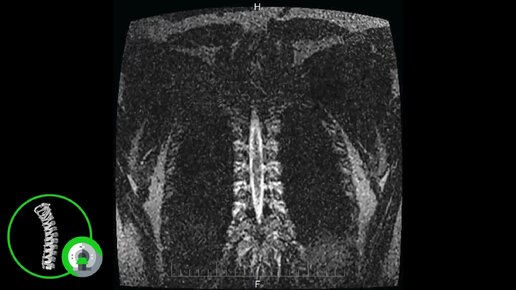

Что покажет МРТ грудного отдела позвоночника